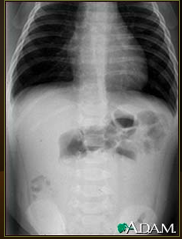

What is this showing?

Intussusception

A loop of bowel has slipped into another section of bowel = swelling, decreased blood flow, obstruction & tissue damage.

Requires emergency treatment (barium enema or surgery).